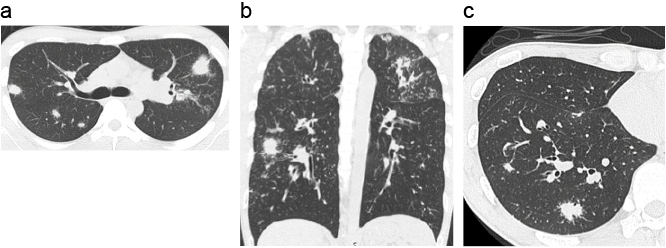

肺サルコイドーシスの治療手順と治療困難時の二次選択薬の使い方

ステロイド薬による治療を行っているときは糖尿病の発病と骨粗鬆症にも注意。

ステロイド薬で十分な効果が得られない下記1~5の重症例では、メトトレキサートなどを用いる。

1. 新しい肺陰影の出現

2. 画像所見の悪化:CTで気管支・血管周囲影の不整、気管支の変形拡張、無気肺の進行を認めたとき

3. 呼吸機能の障害が進行したとき

4. 呼吸器症状の悪化:息切れなどの自覚症状が増悪したとき

5. 他薬剤への変更:ステロイド薬による治療にかかわらず進行する症例ではメトトレキサートの使用を検討する。